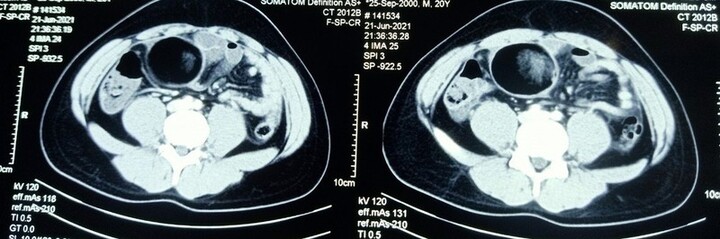

Sau khi về nhà, bệnh nhi nôn liên tục, yếu ớt. Gia đình lo lắng, quyết định đưa bệnh nhi tới Bệnh viện Hữu nghị Việt Đức. Qua khám lâm sàng và chỉ định cận lâm sàng, bệnh nhi được chẩn đoán tắc tá tràng bẩm sinh, ruột quay không hoàn toàn.

Theo thạc sĩ, bác sĩ Hồng Quý Phân, Phó trưởng khoa Phẫu thuật Nhi và Trẻ sơ sinh, đây là trường hợp tắc tá tràng bẩm sinh đến bệnh viện muộn. Do đó, bệnh nhi được chỉ định mổ cấp cứu ngay sau khi có chẩn đoán. Ca phẫu thuật diễn ra trong 1 tiếng đồng hồ. Sau mổ 2 ngày, bệnh nhi bắt đầu được ăn sữa, không còn nôn, đại tiện phân vàng.